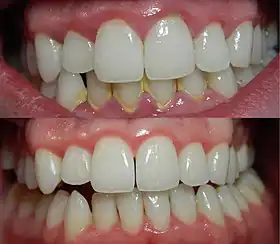

| A severe case of gingivitis | |

Gingivitis is a non-destructive disease that causes inflammation of the gums;[1] ulitis is an alternative term.[2] The most common form of gingivitis, and the most common form of periodontal disease overall, is in response to bacterial biofilms (also called plaque) that are attached to tooth surfaces, termed plaque-induced gingivitis. Most forms of gingivitis are plaque-induced.[3]

Gingivitis is reversible with good oral hygiene; however, without treatment, gingivitis can progress to periodontitis, in which the inflammation of the gums results in tissue destruction and bone resorption around the teeth. Periodontitis can ultimately lead to tooth loss.[6]

The symptoms of gingivitis are somewhat non-specific and manifest in the gum tissue as the classic signs of inflammation:

- Swollen gums

- Bright red gums

- Gums that are tender or painful to the touch

- Bleeding gums or bleeding after brushing and/or flossing

- Bad breath (halitosis)

Additionally, the stippling that normally exists in the gum tissue of some individuals will often disappear and the gums may appear shiny when the gum tissue becomes swollen and stretched over the inflamed underlying connective tissue. The accumulation may also emit an unpleasant odor. When the gingiva are swollen, the epithelial lining of the gingival crevice becomes ulcerated and the gums will bleed more easily with even gentle brushing, and especially when flossing.